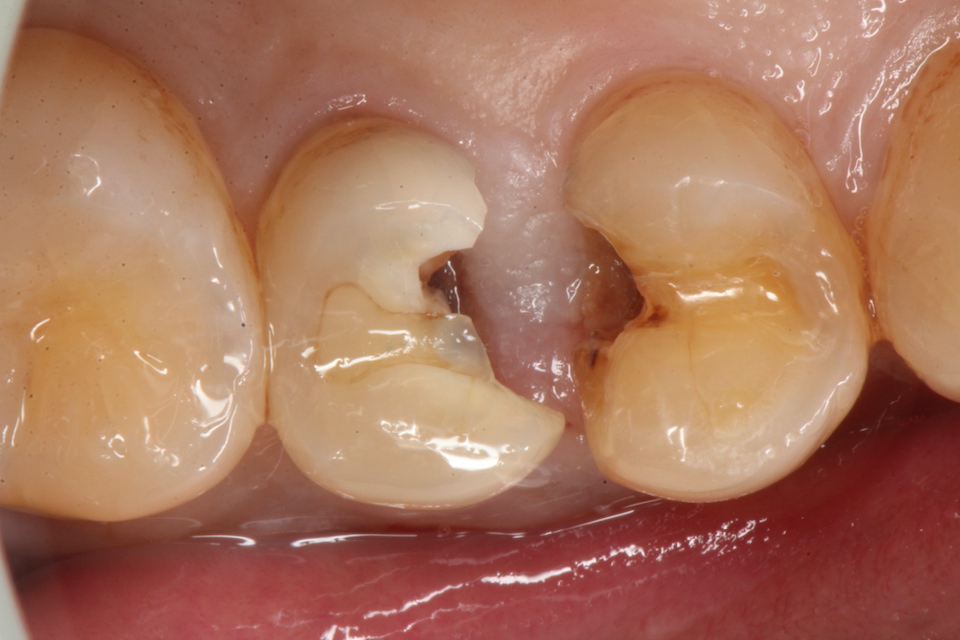

下顎7番の頬側歯茎部カリエスの原因 2025.06.04